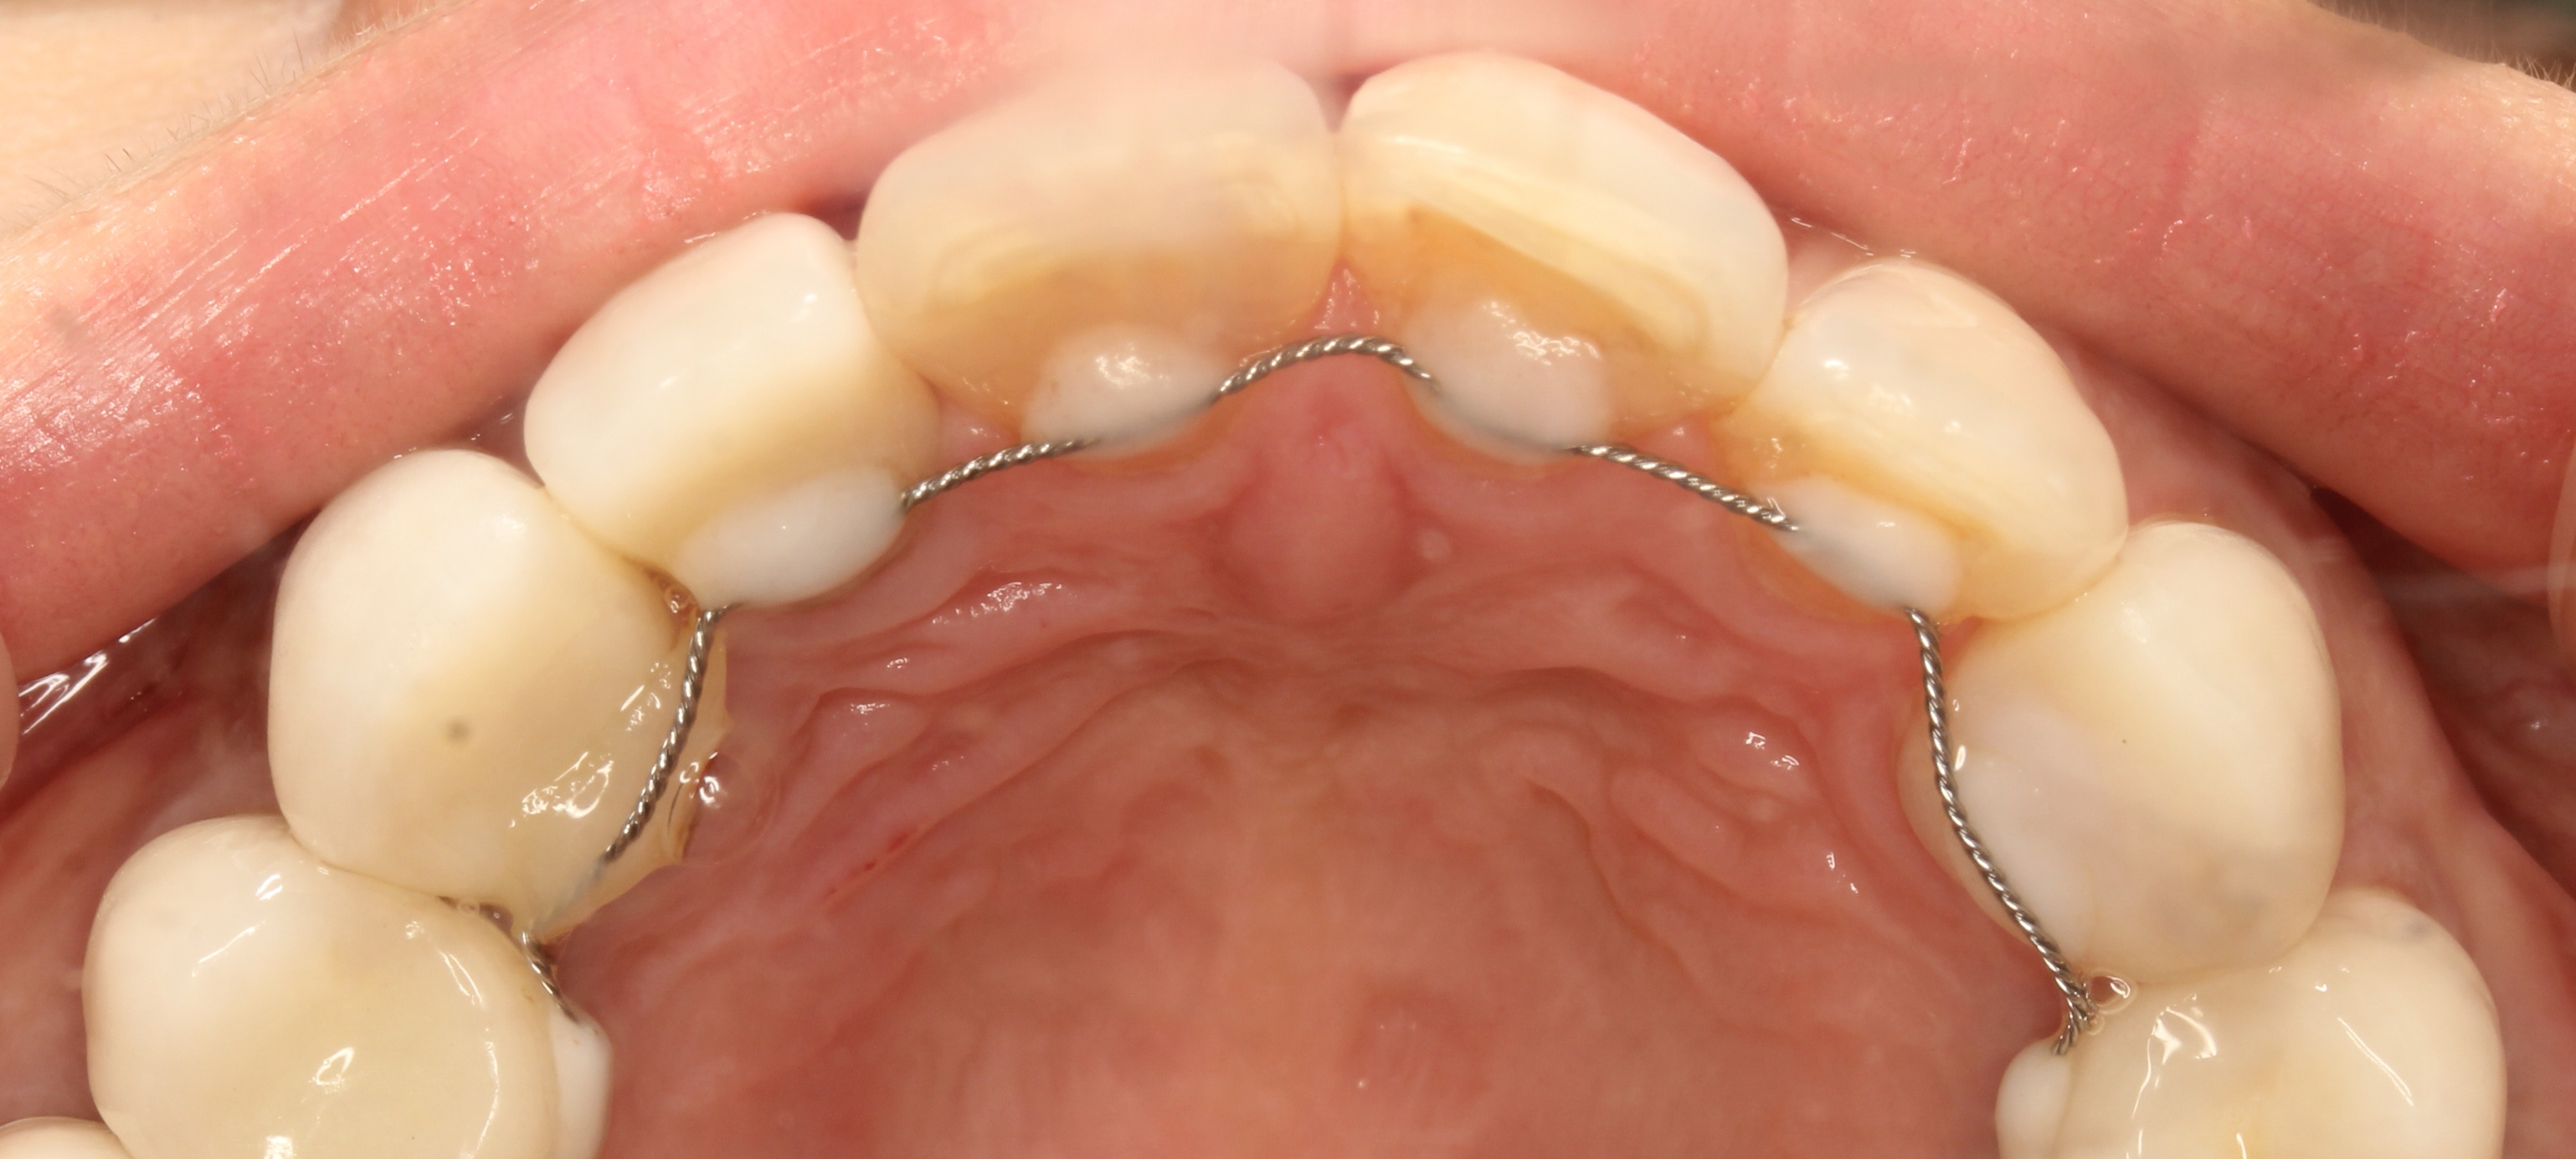

평균 18~36개월이나 걸리는 교정이 완료된 후 치아의 회귀를 막기 위해 유지장치를 착용해야 하는데 이 기간이 정확히 정해져 있지 않다. 다만 치과계는 '유지장치 착용은 길면 길수록 좋다'고 말하고 있으며 그동안 지속적인 관리와 정기검진도 수반돼야 한다.

미니쉬하모니는 요요현상(재발) 없이 기존 치아를 움직이지 않고 치열을 고르게 만드는 치아복구솔루품으로 틈새없이 완벽한 코팅을 통해 내외부의 자극으로부터 자연치아를 안전하게 보호함으로써 치아의 건강까지 되돌려준다.

미니쉬하모니는 긴 교정 기간과 유지장치을 통한 지속적인 관리가 필요하지 않고 단 하루만에 끝난다. 다만, 원데이 미니쉬는 전국 미니쉬멤버스클리닉(MMC) 중에서도 미니쉬치과병원에서만 가능하다. 현재 미니쉬하모니 보철물이 제작되는 치아 디지털 연구소가 미니쉬치과병원과 가장 가깝기 때문이다.